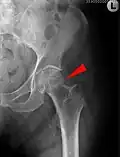

- Zugschraubenosteosynthese bei einer medialen Fraktur. Behandlung einer nicht dislozierten medialen Schenkelhalsfraktur bei einer 92-jährigen Patientin.

-

Aufnahme vor der OP. a.p.-Aufnahme. Die Fraktur ist mit einem Pfeil markiert. -

Seitliche Aufnahme. Die Fraktur ist mit einem Pfeil markiert. -

Nach OP mit Zugschrauben, a.p.-Aufnahme. Man sieht die noch liegende Redondrainage. -

Seitliche Aufnahme.